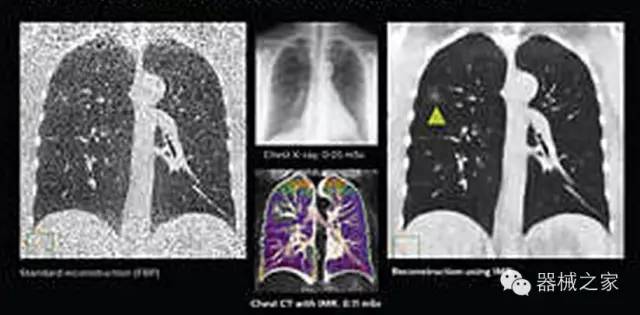

1.低劑量下的胸部顯影

透過數(shù)字化影真芯片DAS系統(tǒng)、球面微平板探測器技術(shù)和濾線柵技術(shù)等硬件技術(shù),整體提高探測器成像的能力,奠定低劑量條件下高清成像的基礎(chǔ);

應(yīng)用目前業(yè)界領(lǐng)先的新一代星光平臺(tái)iDose4 Premium及基于迭代基礎(chǔ)的O一MAR去除金屬偽影技術(shù),達(dá)成微量輻射下零偽影的高清晰成像;